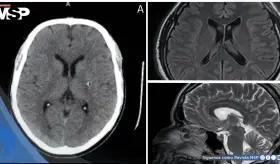

Este caso destaca la importancia de considerar etiologías supratentori...

La cefalea posparto afecta hasta un tercio de las mujeres en la primera semana tras el parto. Aunque la mayoría corresponden a cefaleas primarias benignas, existe una proporción significativa de etiologías secundarias potencialmente graves

Los estudios revelaron anemia microcítica severa (hemoglobina 6.5 g/dL) y neuroimágenes confirmaron trombosis venosa extensa.